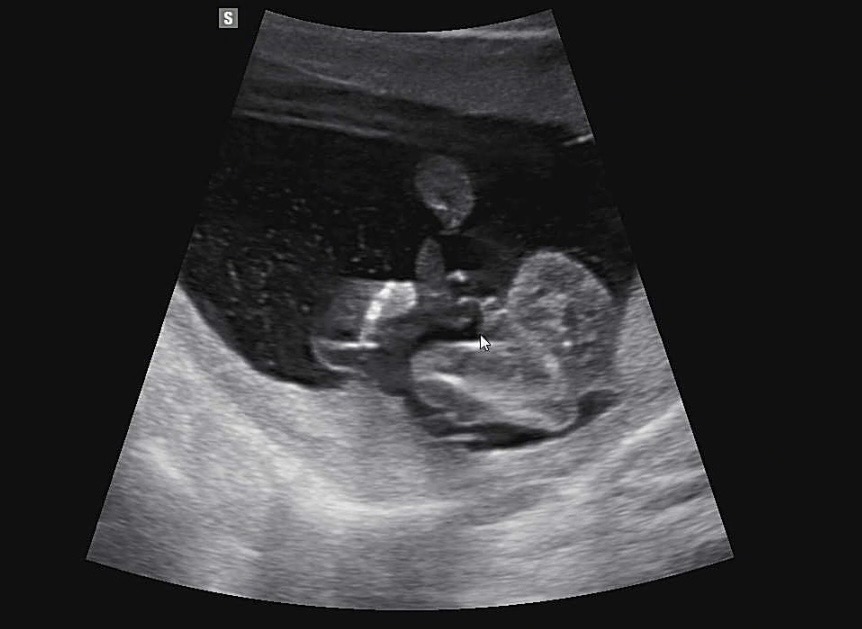

초음파 좀 봐주세요!

오늘 16주2일이며 병원 다녀왔는데 탯줄 때문에 애매하다고는 하셨는데 아들맘 확정일까요?!